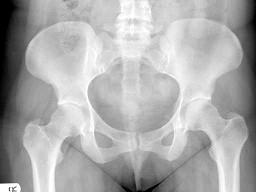

女,根据其正常骨盆影像图像,判断其最可能的年龄?(?)A.53岁左右B.13岁左右C.73岁左右D.33岁左右E.63岁左右

问题 女,根据其正常骨盆影像图像,判断其最可能的年龄?(?)

选项 A.53岁左右 B.13岁左右 C.73岁左右 D.33岁左右 E.63岁左右

答案 D